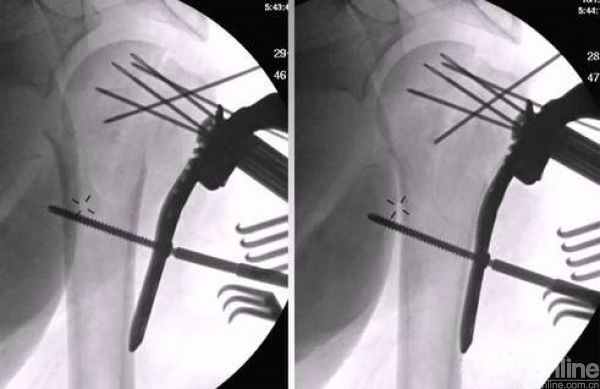

解剖钢板与提拉螺钉的复位

需要注意:不要应用过度提拉,使得内侧肱骨距过复位。

注意完成内侧支撑和内外翻的复位。